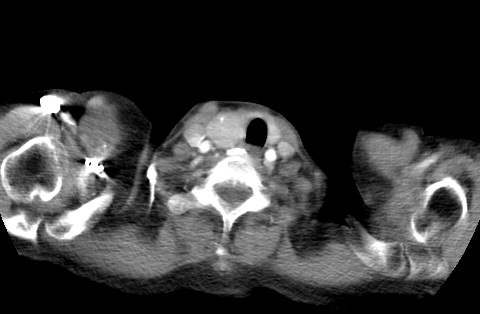

标题: CT23982:女67岁,胸部扫描时发现,甲状腺瘤? [打印本页]

标题: CT23982:女67岁,胸部扫描时发现,甲状腺瘤?

右侧甲状腺腺瘤!支持!不排除甲状腺癌可能!建议手术切除!

右侧甲状腺占位性病变,性质待定(甲状腺腺瘤?);建议:必要时行进一步检查。

右侧甲状腺占位性病变,性质待定(甲状腺腺瘤?);建议穿刺活检。

右侧甲状腺占位性病变,甲状腺腺瘤可能,建议穿刺活检。